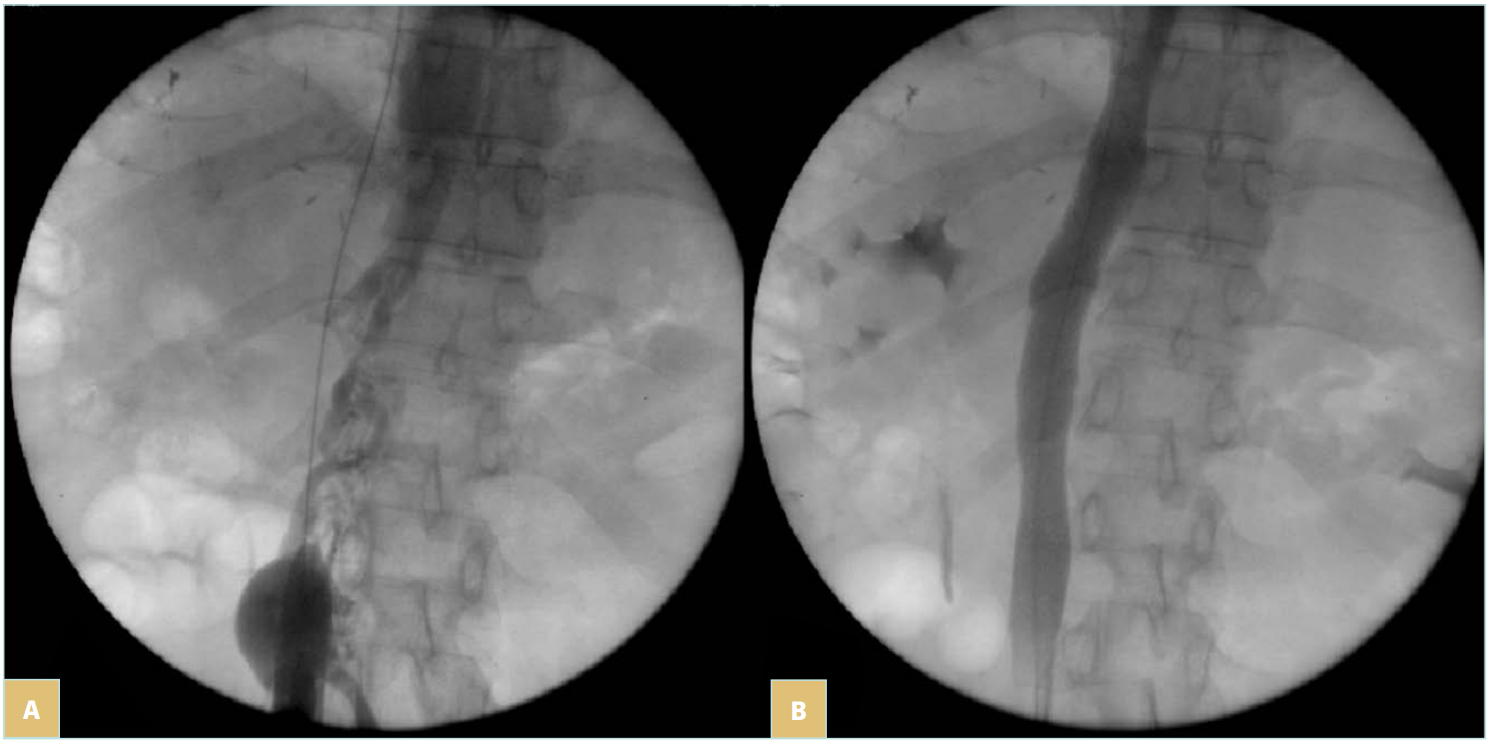

Stenting is then performed using self-expanding stents (Figure 4C and 4D). Different stents were used in the literature. Until 2010, Wallstent (Boston Scientific, Marlborough, Massachussetts, USA) and Gianturco Z stent (Cook Medical, Bloomington, Indiana, USA) were the 2 most used stents. Since the development of nitinol self-expanding stents, many others have become available, though some of them are designed for femoro-iliac veins (Venovo, Abre). Stent sizing depends not only on the diameter of the adjacent nonpathologic IVC size—that can be evaluated by CT scan or IVUS—but also to the tumor. In most cases 18 to 22 mm in diameter should be used for the IVC as larger stents can have difficulties with expanding; too-small stents can migrate and also limit flow. Few nitinol stents are available in 20-mm diameter or higher (see Table I). These stents have a more precise deployment than the Wallstent without foreshortening. Regarding stent length, they should cover at least 15 to 20 mm beyond the obstructive lesion at both ends, covering an area that goes not only from healthy-to-healthy segment but also includes a safety margin to avoid restenosis by tumor progression.9,10 When multiple stents are needed, an overlap of at least 20 mm should be used. In case of biiliocaval lesions, different stent configurations can be used: the Eiffel tower configuration while deploying the IVC stent first, then both iliac stents simultaneously (Figure 4D), or a double-barrel technique (mostly if lesions are limited to the iliocaval confluence).

Figure 4. 76-year-old man suffering from right iliac and inferior vena cava (IVC) compression by iliac and infrarenal IVC nodes and liver metastasis from urothelial cancer with ascites (history of cystectomy and right uretero-nephrectomy): A) compression of the right iliac vein and infrarenal IVC; B) compression of the suprarenal IVC; C) after angioplasty and stenting of the suprarenal IVC; a guidewire (arrow) was positioned in the suprahepatic vein before stent deployment; D) after

biiliocaval stenting according to the Eiffel tower technique.